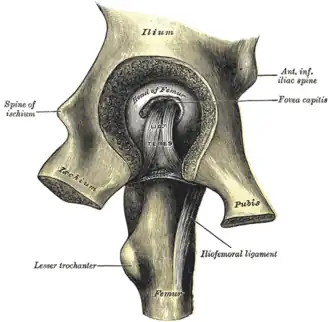

Left hip-joint, opened by removing the floor of the acetabulum from within the pelvis.

Left hip-joint, opened by removing the floor of the acetabulum from within the pelvis. -